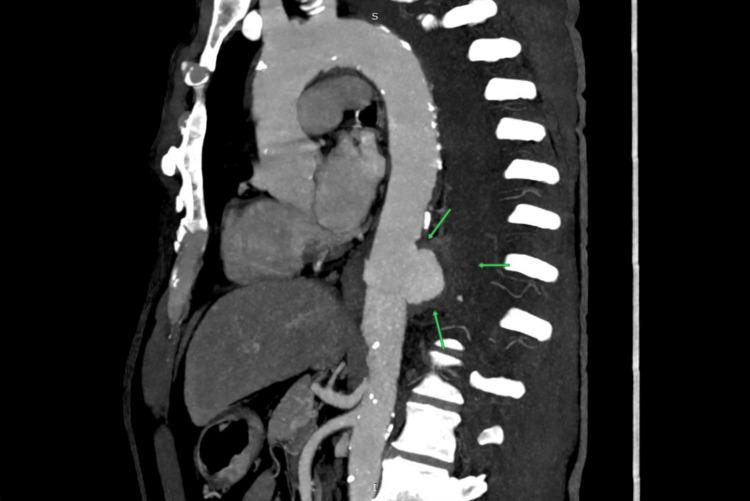

The rupture of a descending thoracic aortic aneurysm (DTAA) is a rare but critical vascular emergency that requires immediate recognition and action. It usually presents as a sharp, severe pain in the chest or back; however, some individuals exhibit non-typical symptoms resembling respiratory infections, leading to misdiagnosis and delays in definitive treatment. A 63-year-old male with a history of hypertension and smoking presented with left-sided chest pain to another hospital, where he was diagnosed with unstable angina based on clinical suspicion and managed conservatively with anti-anginal medication. Over the next three days, the patient developed a persistent cough, low-grade fever, and pleuritic pain, prompting referral to our hospital, where a lower respiratory tract infection (LRTI) was considered. On arrival, he was hemodynamically stable with a systolic BP of 100 mmHg and was managed with intravenous fluids, antibiotics, and nebulizers. Chest X-ray revealed moderate left pleural effusion with tracheal deviation, and thoracic ultrasound confirmed internal echoes suggestive of hemorrhagic content. Diagnostic thoracentesis yielded hemorrhagic fluid, prompting high-resolution computed tomography (HRCT), which showed a partially thrombosed 54 mm × 49 mm saccular aneurysm of the descending thoracic aorta with left lung collapse. Despite the rupture, the patient remained hemodynamically stable, suggestive of a contained event. A subsequent computed tomography angiogram (CTA) confirmed rupture into the pleural space and was the imaging modality that established the final diagnosis. The patient underwent thoracic endovascular aortic repair (TEVAR) using a 30 mm × 30 mm × 120 mm Ankura graft, selected for its conformability and effective sealing profile in emergencies. Postoperative recovery was uneventful. A CT aortogram on day three confirmed complete exclusion of the aneurysm with no endoleak, and a follow-up chest X-ray at two weeks showed full resolution of the hemothorax. This case illustrates the diagnostic challenge posed by atypical ruptured DTAA presentations and reinforces the importance of early CTA in unexplained pleural effusions, even in stable patients. Structured post-TEVAR surveillance remains critical to ensure long-term outcomes.

降主动脉瘤(DTAA)破裂是一种罕见但危急的血管急症,需要立即识别并采取行动。其通常表现为胸部或背部突发剧痛;然而,一些患者会出现类似呼吸道感染的非典型症状,导致误诊及确定性治疗延误。一名63岁男性,有高血压和吸烟史,因左侧胸痛前往另一家医院就诊,基于临床怀疑被诊断为不稳定型心绞痛,并接受抗心绞痛药物保守治疗。在接下来的三天里,患者出现持续咳嗽、低热和胸膜炎性疼痛,遂转诊至我院,当时考虑为下呼吸道感染(LRTI)。入院时,他血流动力学稳定,收缩压为100 mmHg,接受了静脉输液、抗生素和雾化治疗。胸部X线显示左侧中等量胸腔积液伴气管偏移,胸部超声证实内部回声提示为血性成分。诊断性胸腔穿刺抽出了血性液体,促使进行高分辨率计算机断层扫描(HRCT),结果显示降主动脉有一个54 mm×49 mm的部分血栓形成的囊状动脉瘤,伴左肺萎陷。尽管已经破裂,但患者血流动力学仍保持稳定,提示为局限性事件。随后的计算机断层血管造影(CTA)证实动脉瘤破裂进入胸腔,这一成像方式确立了最终诊断。患者接受了胸主动脉腔内修复术(TEVAR),使用了一枚30 mm×30 mm×120 mm的安珂拉移植物,选择该移植物是因其顺应性好且在紧急情况下具有有效的密封性能。术后恢复顺利。术后第三天的CT主动脉造影证实动脉瘤完全被隔绝,无内漏,术后两周的胸部X线随访显示血胸完全吸收。该病例说明了非典型破裂DTAA表现所带来的诊断挑战,并强调了早期CTA在不明原因胸腔积液中的重要性,即使是在病情稳定的患者中。TEVAR术后的结构化监测对于确保长期疗效仍然至关重要。